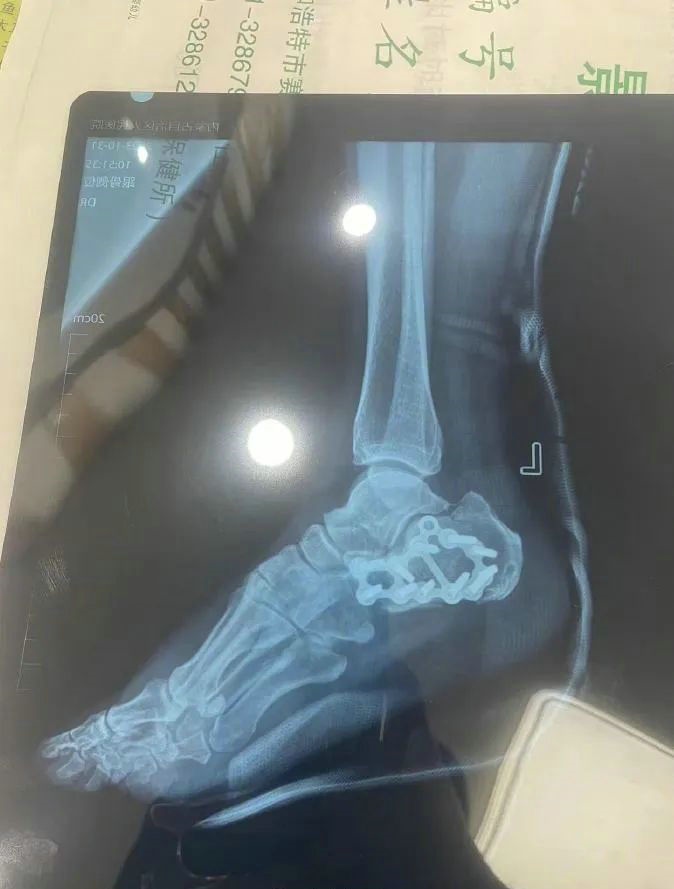

“那時候我剛工作了兩天,在第三天10月22日下午施工過程中從三層高的鐵架上摔了下來,導致30厘米左右的鋼筋刺穿我的右側(cè)臀部,左腳跟也粉碎性骨折,被送往內(nèi)蒙古自治區(qū)人民醫(yī)院救治,當晚做了手術(shù)取出刺在右臀部的鋼筋,10月30日又進行了左腳粉碎性骨折手術(shù)。”雷先生告訴記者。